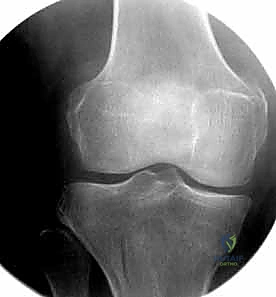

الهدف الأول والأخير في علاج هذه الحالات هو استعادة المحاور الميكانيكية والتشريحية الطبيعية للطرف السفلي، وضمان استقامة السطح المفصلي للعظم وطوله ومحاذاته بشكل عام، لضمان عودة المريض إلى ممارسة حياته الطبيعية بدون ألم أو إعاقة.

عند حدوث كسر في هذه المنطقة، تختل هذه المحاور الدقيقة، مما يؤدي إلى توزيع غير متساوٍ للضغط على غضاريف الركبة. إذا لم يتم إصلاح هذا الخلل جراحياً بدقة متناهية، فإن المريض سيكون عرضة للإصابة بخشونة الركبة المبكرة (Post-traumatic Osteoarthritis).

- الأشعة المقطعية (CT Scan): وهي ضرورية جداً في كسور عظم الفخذ البعيدة، خاصة إذا كان الكسر يمتد إلى داخل مفصل الركبة (Intra-articular fractures). تساعد الأشعة المقطعية الدكتور هطيف على بناء نموذج ثلاثي الأبعاد للكسر، مما يسهل التخطيط الجراحي وتحديد أماكن وضع المسامير بدقة.